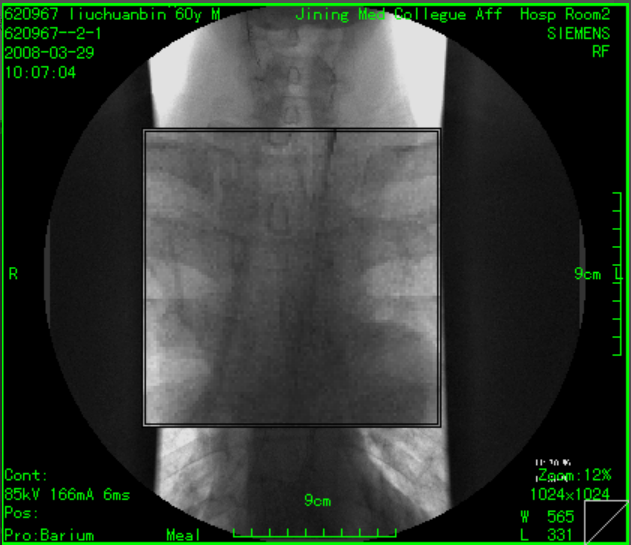

二维图像处理:支持图像无级缩放、图像旋转、翻转、图像移动漫游、图像黑白翻转、伪彩、放大镜、图像复制、窗宽、窗位调节、预设窗宽/窗位、ROI自动窗宽、窗位调节、窗宽、窗位曲线调节、显示双窗宽/窗位、测量、标记、距离测量、角度测量、椭圆测量、任意形状面积测量、文字注释、图形、箭头标注、可手画线、长度、面积计算显示、ROI平均密度值测量:圆形、矩形等、图像拼接、图像增强、心胸比测量;

2、影像诊断与分析:医生可以利用PACS系统进行影像的放大、旋转、对比度调节等操作,以获得更清晰的诊断结果。

3、临床诊断:医生可以通过PACS系统查看和分析患者的影像,辅助诊断疾病。